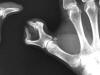

Carpo normal

ACT Alteraciones degenerativas en muñeca.

Artritis psoriásica y falange bífida.

Artritis psoriásica.

Falange distal de dedo 1º de mano, bífida.